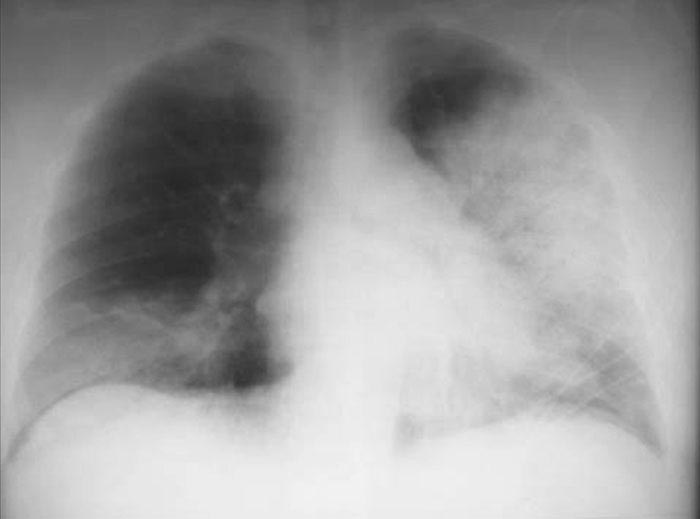

Corticoides en la neumonía severa

La actualización de una revisión Cochrane muestra beneficio del uso de corticosteroides en pacientes internados con neumonía severa. The Cochrane Library, 13 de diciembre de 2017